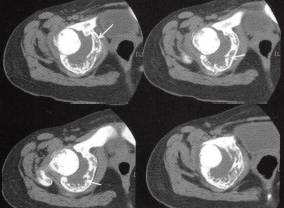

图1右盆骨软骨母细胞瘤

A

B

C

D

【影像学检查】

A.CT平扫见髋臼骨质弥漫性小片状低密度病灶,残存骨小梁,多处骨嵴,外缘关节面侧骨皮质连续性断裂、缺失,内缘骨皮质连续性断裂并伴少许骨膜反应,病灶向关节腔内侵犯较明显,关节腔明显积液;